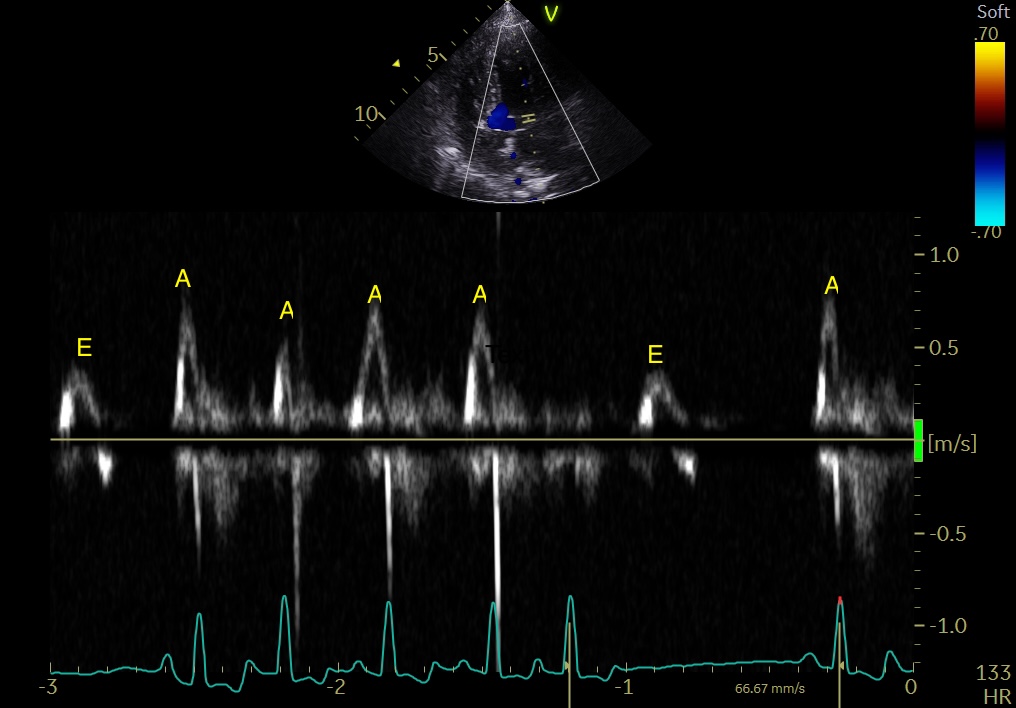

超声心动图

超声心动图显示左心室收缩减弱,并伴有运动异常(dyskinesia,不受控的运动)。但未见扩张型心肌病(大型犬常见的心肌疾病)。收缩功能减弱被认为与持续的快速且不规则的心律有关。